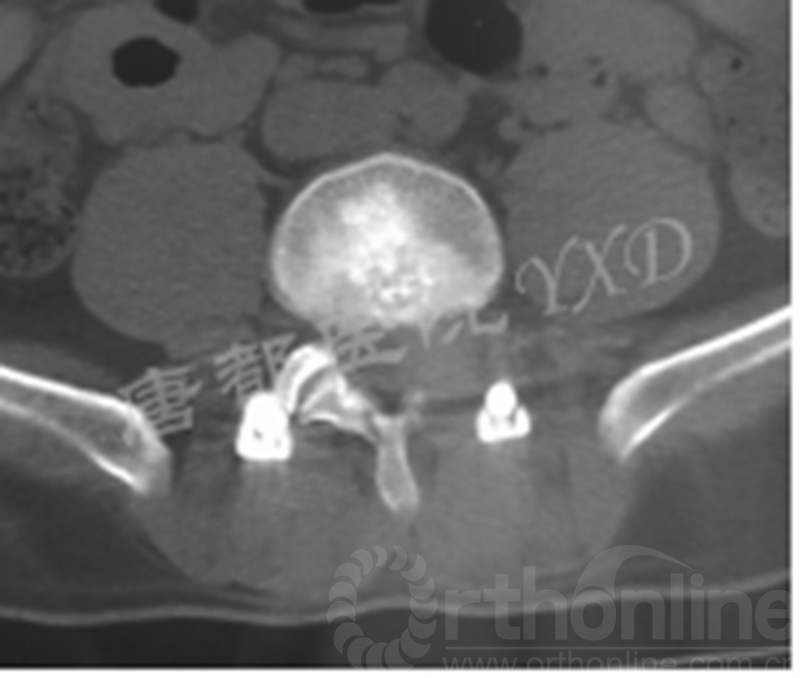

患者47岁,男性。

主诉:腰椎术后左下肢疼痛2月。

专科情况:跛行入病房;左侧直腿抬高试验阳性(60°)、加强试验阳性;左侧足背伸肌力、踇趾背伸肌力3级;左小腿外侧及足背皮肤感觉明显减退;余未见明显异常。VAS评分:左下肢7~8。

既往于半年前因“腰椎间盘突出症(L4-5)”于外院行腰椎侧路脊柱内镜下髓核摘除术(L4-5)。后因症状复发,分别在2周前、10天前于外院行两次腰椎后路脊柱内镜下髓核摘除术(L4-5)。

影像学检查:

诊断:腰椎间盘突出症术后复发

手术方案:显微镜辅助MI-TLIF腰椎翻修术

术中视频:http://api.orthonline.com.cn/attach/Case2.mp4(术中发现因前三次侧路及后路内镜手术的操作,术区大量瘢痕组织增生、与神经粘连严重;此外,摘除头侧游离髓核时连接有软骨终板脱落;在显微镜操作下,安全地将神经进行充分松解,压迫神经的游离髓核及软骨终板彻底清除。无手术并发症)